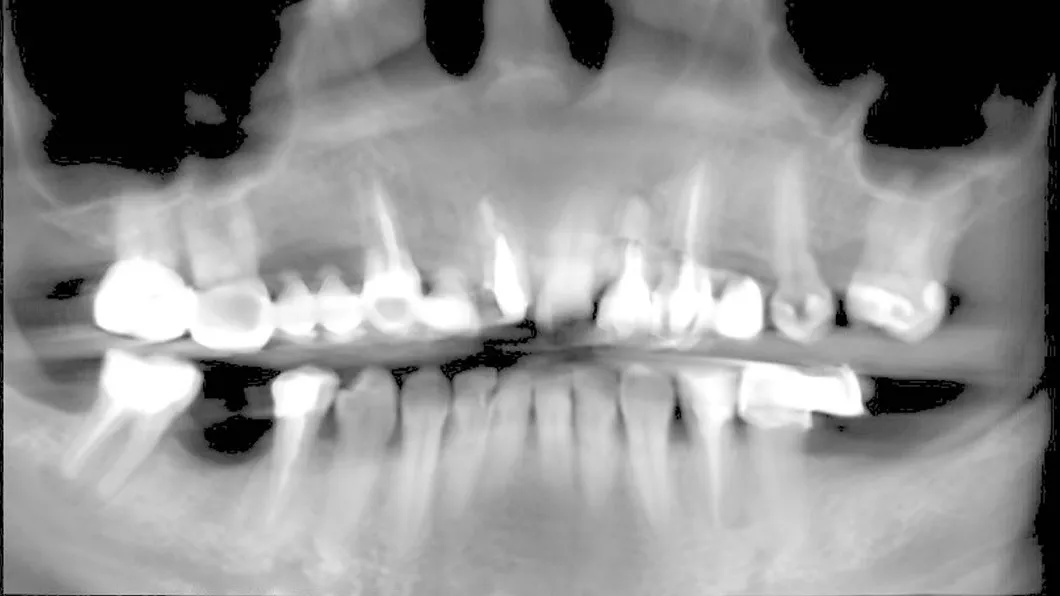

Клинический случай 3 имплантация зубов

Пациентка обратилась с жалобами на неудовлетворительный внешний вид старых коронок и мостовидных протезов, а так же дискомфорт и боль при жевании, в связи со значительной подвижностью конструкций.

Ситуация до